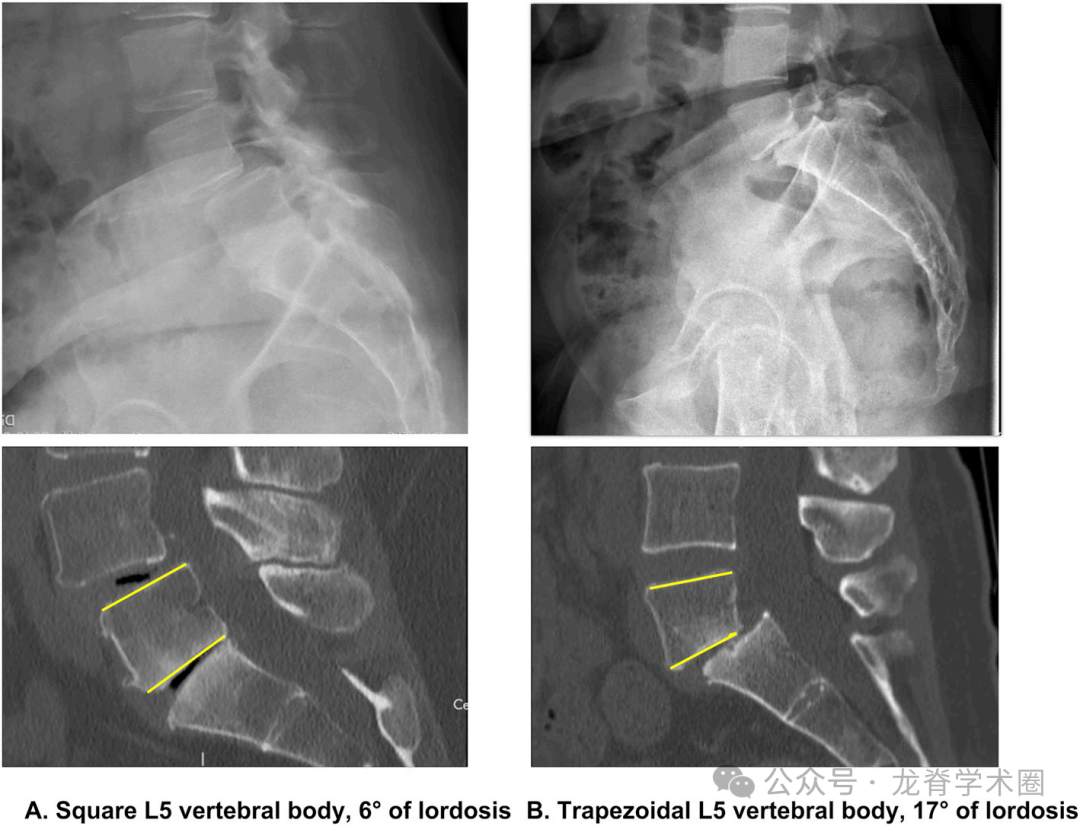

LL是维持直立姿势的关键组成部分。Vaz等人证明椎间盘比椎体塑形更能实现腰椎前凸。Been等人也证实了这些结果,并注意到随着LL过渡到胸椎后凸,下腰椎从增加的前凸到轻微的上腰椎后凸的进展。这种转变通常发生在腰2椎体,尽管这受到矢状面序列正常变化的影响。此外,矢状面序列的变化也影响身体和椎间盘产生的前凸的相对比例。

Roussouly等人首先描述了基于SS正常变化的腰椎不同形态。在这项工作中,Roussouly等人重新证明了一个早期的发现,显示整体的LL与SS和PI显著相关。PI在整个骨骼成熟过程中随着骨盆的前后生长而增加,直到成年后变得固定,范围从20°到>80°。PI被认为成年后保持不变,即使有退化。然而,最近的数据显示,PI实际上可能会随着时间的推移而改变,通过骶髂关节的压力增加以及随后这些关节和骶骨终板的重塑,这一过程在涉及S1作为下固定椎体的长节段融合患者中很明显。然而,考虑到PI相对于SS的稳定性,LL通常相对于PI进行评估。在无症状的受试者中,PI影响LL的大小和分布;与低PI的受试者相比,PI较大的受试者骶骨角度更大,SS更高,LL更大。LL也与胸后凸相关。因此,基于其与PI和胸后凸的关系来评价LL是有利的。

多年来,定义LL的手术目标一直在变化。曾经的目标是“尽可能多的前凸”。这种情况一直持续到几位作者,包括Schwab等人和Lafage等人提出PI与LL在10°内匹配。如果PI低,建议将LL校正为PI+10°,如果PI高,建议将LL校正为PI-10°。PI-LL概念已经发展到针对理想的腰椎顶点和头尾部节段之间的前凸分布。这些测量在退行性腰椎中尤为重要,因为即使整体前凸看起来正常,患者的LL也可能很差。Pesenti等人确定了正常人脊柱前凸的区域分布。L4-S1前凸和L1-L4前凸占整体前凸的百分比随PI的变化而变化,随着PI的增加,头侧前凸对整体前凸的贡献增加。他们的研究也建立在Roussouly等人的工作基础上,并再次证明,随着PI的增加,前凸的顶点会迁移到更偏向头端的位置,同时前凸的近端程度也会随之增加。值得注意的是,作者对尾侧和头侧前凸的定义不同。Roussouly等人将头侧前凸定义为近端前凸,根据椎体PI的不同而不同。然而,为了简化概念,Pesenti等人分析了L1-L4和L4-S1的前凸。这些在退行性脊柱疾病中的应用已被证明可以降低术后矢状位失衡、邻近节段退变和翻修手术的风险。最近的研究进一步加深了对矢状位平衡的理解,报道了基于PI的节段的平均前凸值,然而,手术计划应根据每位患者的脊柱骨盆解剖结构进行个性化分析。例如,在低PI的情况下,近端腰椎后凸是正常的,对于大多数患者来说,T10-L2中立对齐是合适的。